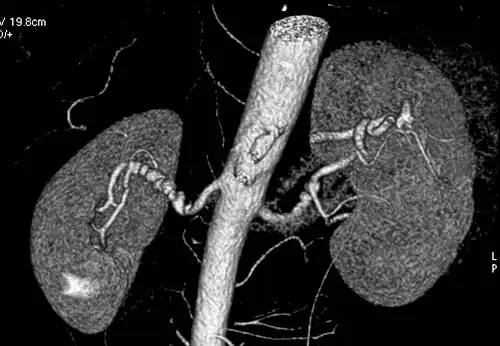

Volume rendered CTA of renal arteries in patient with medial fibromuscular dysplasia

Visualization of blood flow in the renal arteries (those supplying the kidneys) in patients with high blood pressure and those suspected of having kidney disorders can be performed using CTA. Stenosis (narrowing) of a renal artery is a cause of hypertension (high blood pressure) in some patients and can be corrected. A special computerized method of viewing the images makes renal CT angiography a very accurate examination.[6] CTA is also used in the assessment of native and transplant renal arteries.[3] While CTA is great for imaging of the kidneys, it lacks the ability to perform procedures at the same time. Thus traditional catheter angiography is used in cases of acute renal hemorrhage or acute arterial obstruction.[2]